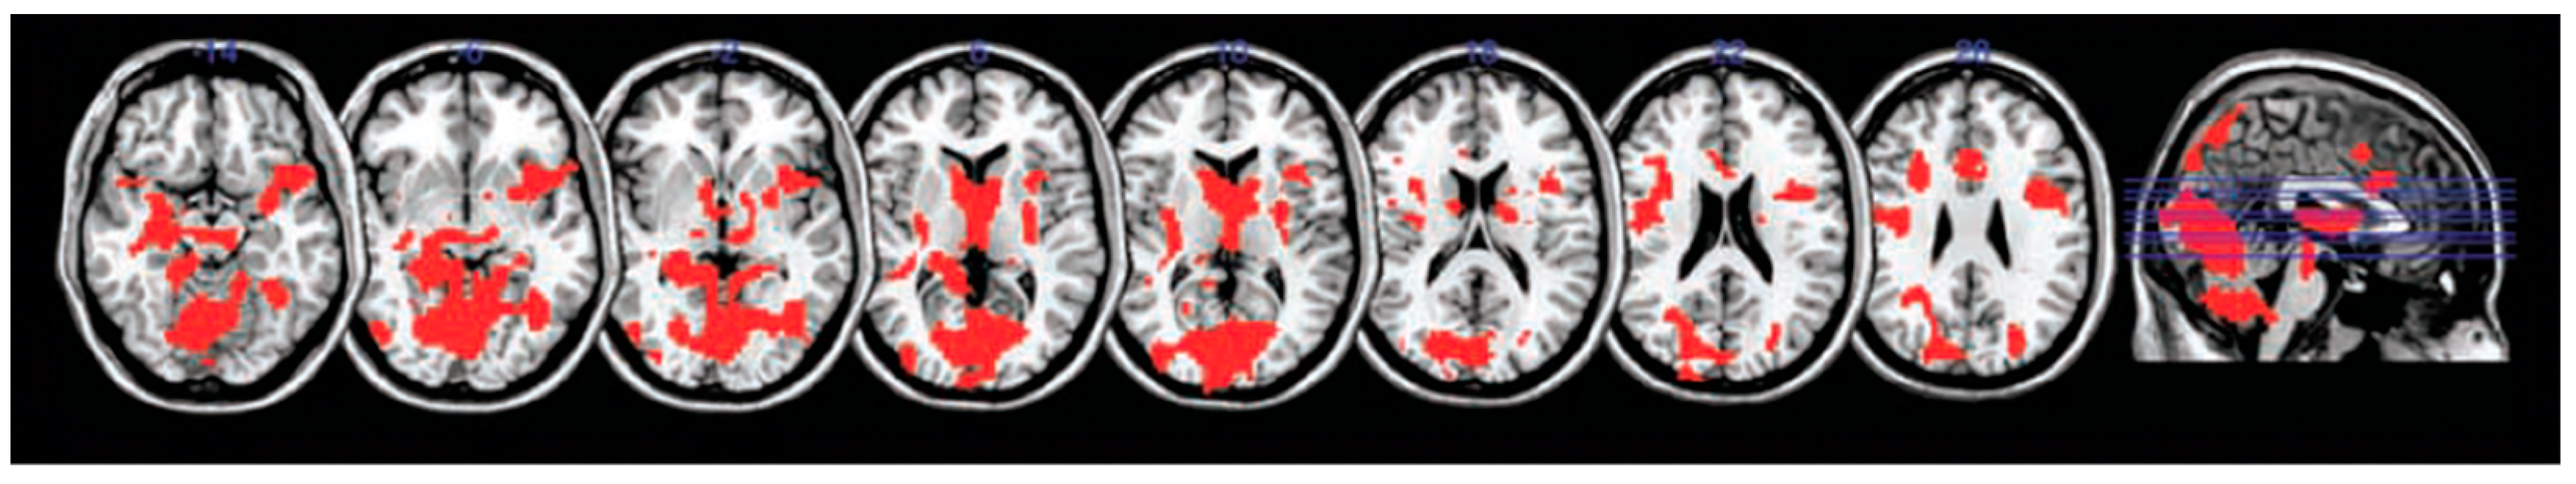

Figure 1.

Regions commonly activated during memory recollection, comprising the recollection networks.

An early study of fMRI neural dynamics and memory performance identified significantly greater activity across broad regions of the recollection network (Figure 1) in Ch+ breast cancer survivors performing a delayed verbal memory recognition task. Hyperactivity was observed in left hippocampus, bilateral parahippocampus gyri, right superior temporal gyrus, bilateral precuneus, right cingulate gyrus, and throughout several regions of the frontal lobes (Figure 3) [111]. The recognition accuracy of Ch+ breast cancer survivors was comparable to healthy controls. These results suggest that successful memory processing following chemotherapy is supported by compensatory over-recruitment of key nodes of the temporal lobes and the recollections network, reflective of inefficient neural processing. See Table 2 for a summary of fMRI studies showing chemotherapy-related disruptions in the hippocampus and temporal lobes during performance of memory tasks.

Many of the neural regions identified as comprising the recollection network overlap with nodes of the default mode network (DMN). The DMN is a collection of brain regions that are active when engaged in passive, internally focused cognition (mind wandering) or during a resting state [158,159,160,161,162]. During rest or mind wandering, the brain engages in recollection and in future thinking (planning, imagining) [137,163]. Neuroimaging studies have shown that both future thinking and recollection engage the same core network of brain regions including the mPFC, lateral and medial temporal regions (hippocampus and parahippocampal cortex), and lateral and medial parietal regions (precuneus and retrosplenial cortex) (Figure 1), suggesting a similar underlying neural mechanisms mediating past and future memory processing [137,163,164,165,166,167]. This common DMN/recollection network engaged during mind wandering is an adaptive process that has been proposed to integrate and recombine associations from experiences stored in episodic memory to predict possible future situations in a process of ‘constructive episodic simulation’ [137,168,169].